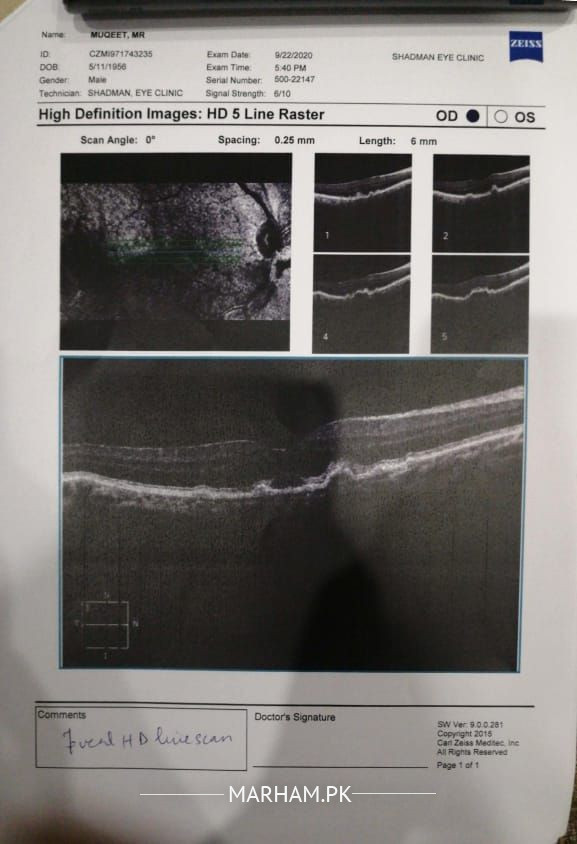

A.a, i have attached my father's OCT reports for right eye. He has lost almost all vision in his left eye due to retinal hemorrhagic detachment about 3 months ago. My father also has cataract problem in his both eyes. Now, gradually his eye sight of right eye is also getting weaker, he used to wear 3.5 number glasses 3 months back but now he cant see properly with even glasses on. he has consulted doctor for lens change in his right eye due to cataract. Doc advised to get OCT for right eye and after getting results, he has told that the condition of right eye is getting same as of left one, retina of right eye has been tilted and he did not advice to change lens as according to him, pressure might damage the retina. He only gave him grid and told him to inform if he sees distorted lines on it... Can any doctor please suggest, if there is anything he can do to improve his vision of right eye or to prevent the condition from getting worse or same like left eye... Can he get his lens ch

This seems Like a case of choroid neovascularization. My dear u need to get an OCT angiography done plus consult a surgeon. There should be series of intravitreal injections needed for this plus supportive treatment. If u are in Lahore consult mayo hospital dr zahid Kamal he will guide u

W.A I have seen your OCT report of right eye, according to Oct there have retinal changing as tilting of fundus, if your father have suger or BP you have to control it, if you want to increase his vision you must go to Low vision dept. Al shifa eye trust, known as Light House, catract surgery is not good decision. Don't leave him alone